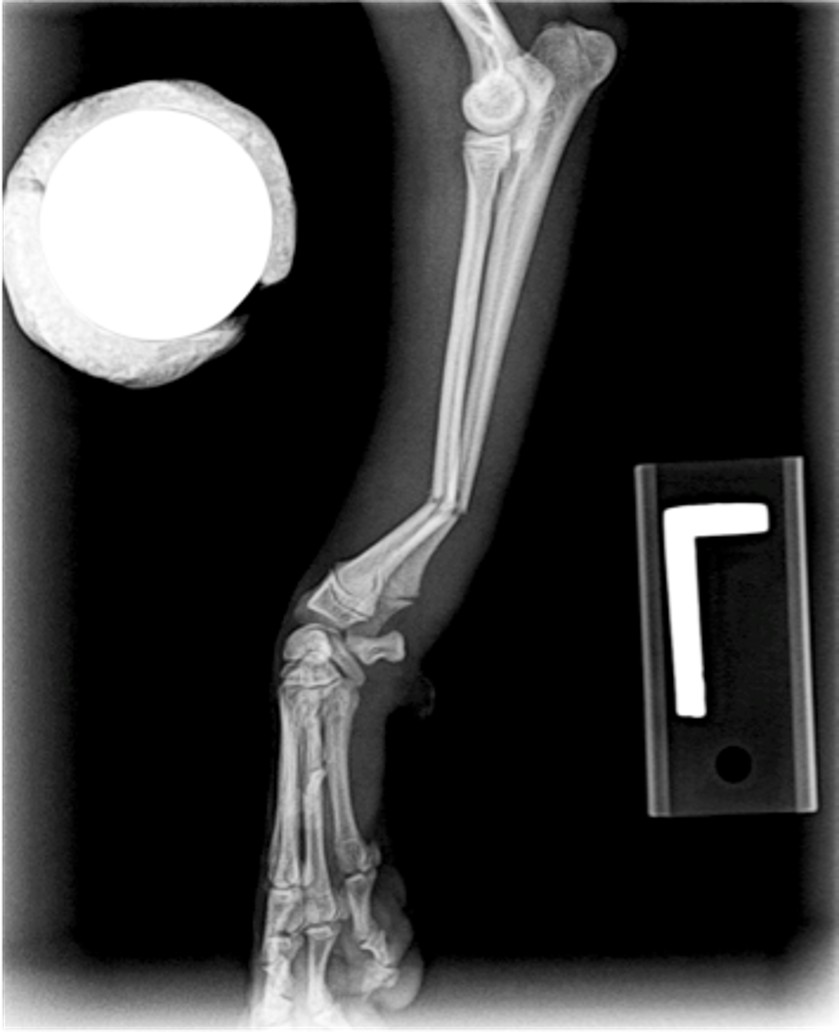

Radiography - fractured radius/ulna